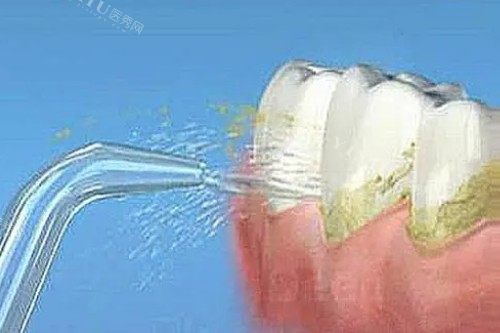

喷砂洗牙:价格约250-600元起

在超声波基础上,通过喷砂粉去除牙齿表面的色素沉积(如烟渍、茶渍、咖啡渍),适合长期吸烟或饮用深色饮料的人群。医院报价约250-400元,私立高端门诊(如青岛可恩口腔)可能达300-500元。

喷砂洗牙:美白需求推动价格上浮

喷砂洗牙的核心优势在于去除外源性色素,适合对牙齿洁白度有较高要求的人群。其价格比超声波洗牙高30%-50%,主要源于喷砂粉成本及操作精细度要求。例如,青岛瑞泰口腔喷砂洗牙套餐(含抛光)约450元,而单纯超声波洗牙需要280元。